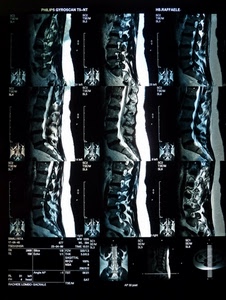

1057° Colonna vertebrale

Voto: 25.82 |